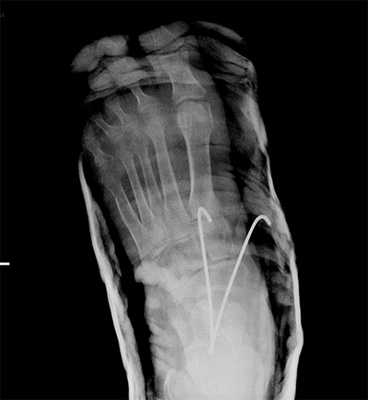

При смещении более 2 мм, нестабильности при функциональных тестах - рекомендовано открытое устранение вывиха с жёсткой фиксацией винтами или пластинами. Используются один или два продольных доступа в 1 и 2 межплюсневых промежутках. После обнажения первого предплюсне-плюсневого сустава первым этапом устраняется межклиновидная нестабильность, вторым этапом устраняется предплюсне-плюсневая нестабильность. В послеоперационном периоде сразу начинается разработка активного объёма движений. Нагрузку на стопу начинают постепенно, с тем чтобы полностью её восстановить к 6-8 неделе. Удаление спиц Киршнера производится через 6-8 недель, компрессирующих винтов через 3-6 месяцев. Возвращение к полной физической активности не ранее 9-12 месяцев после операции.

Открытое вправление вывиха, трансартикулярная фиксация 1-2-3 предплюсне-плюсневых суставов винтами.

В случаях этого повреждения показано оперативное лечение, открытое устранение подвывиха основания 2 плюсневой кости с фиксацией винтом. Устранение подвывиха производится из доступа в 1 межплюсневом промежутке, рубцовая ткань и остатки связки могут интерпонировать сустав, тогда потребуется их удалить. После вправления производится предварительная фиксация спицей и рентгенологический контроль.

Затем устанавливается винт соединяющий основание 2 плюсневой кости и медиальную клиновидную кость.